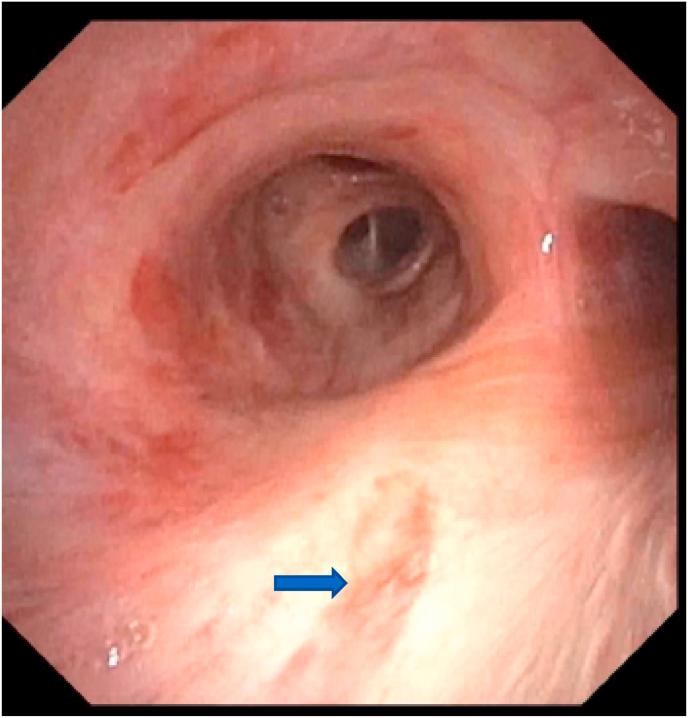

Barriers posed by the COVID-19 pandemic have led to reduced access to Human Immunodeficiency virus (HIV) care, leaving untreated patients at risk for various superimposed infections and malignancies such as Kaposi sarcoma (KS). We recently encountered a 37-year-old African-American male with a past medical history of HIV who tested positive for SARS-CoV-2 and was diagnosed with AIDS-related disseminated KS, representing the first reported case of COVID-19 infection with a newly diagnosed concomitant KS. The patient experienced multi-organ failure requiring tracheostomy, renal replacement therapy, and a prolonged intensive care unit (ICU) stay. Goals of care were changed to comfort measures and the patient passed away shortly afterwards. He was made comfort measures and passed away shortly afterwards. AIDS-related KS is a vascular tumor seen in association with (HHV-8). Management of limited AIDS-related KS typically includes combined antiretroviral therapy (ART) while multi-organ KS disease demands systemic chemotherapy. Immunosuppression should be avoided in patients with AIDS-related KS as it can lead to progression of KS. This recommendation is in conflict with the usual standard of care for patients with COVID-19 pneumonia, requiring clinical judgment and a customized approach based on the stage and severity of both the KS and the COVID-related disease. We briefly review HIV-COVID-19 coinfection, AIDS related KS and challenges associated with their management.

2019年冠状病毒病(COVID-19)大流行造成的障碍导致获得人类免疫缺陷病毒(HIV)治疗的机会减少,使未经治疗的患者面临各种叠加感染和恶性肿瘤的风险,如卡波西肉瘤(KS)。我们最近遇到一名37岁的非裔美国男性,他有HIV病史,SARS-CoV-2检测呈阳性,被诊断为艾滋病相关播散性KS,这是首例报告的COVID-19感染合并新诊断KS的病例。该患者出现多器官功能衰竭,需要气管切开、肾脏替代治疗,并在重症监护病房(ICU)长期住院。护理目标改为采取舒适措施,患者随后不久去世。对他采取了舒适措施,他随后不久去世。艾滋病相关KS是一种与人类疱疹病毒8型(HHV-8)相关的血管肿瘤。局限性艾滋病相关KS的治疗通常包括联合抗逆转录病毒疗法(ART),而多器官KS疾病则需要全身化疗。艾滋病相关KS患者应避免免疫抑制,因为这可能导致KS进展。这一建议与COVID-19肺炎患者的通常护理标准相冲突,需要根据KS和COVID相关疾病的阶段和严重程度进行临床判断并采取定制方法。我们简要回顾了HIV与COVID-19合并感染、艾滋病相关KS及其管理相关的挑战。